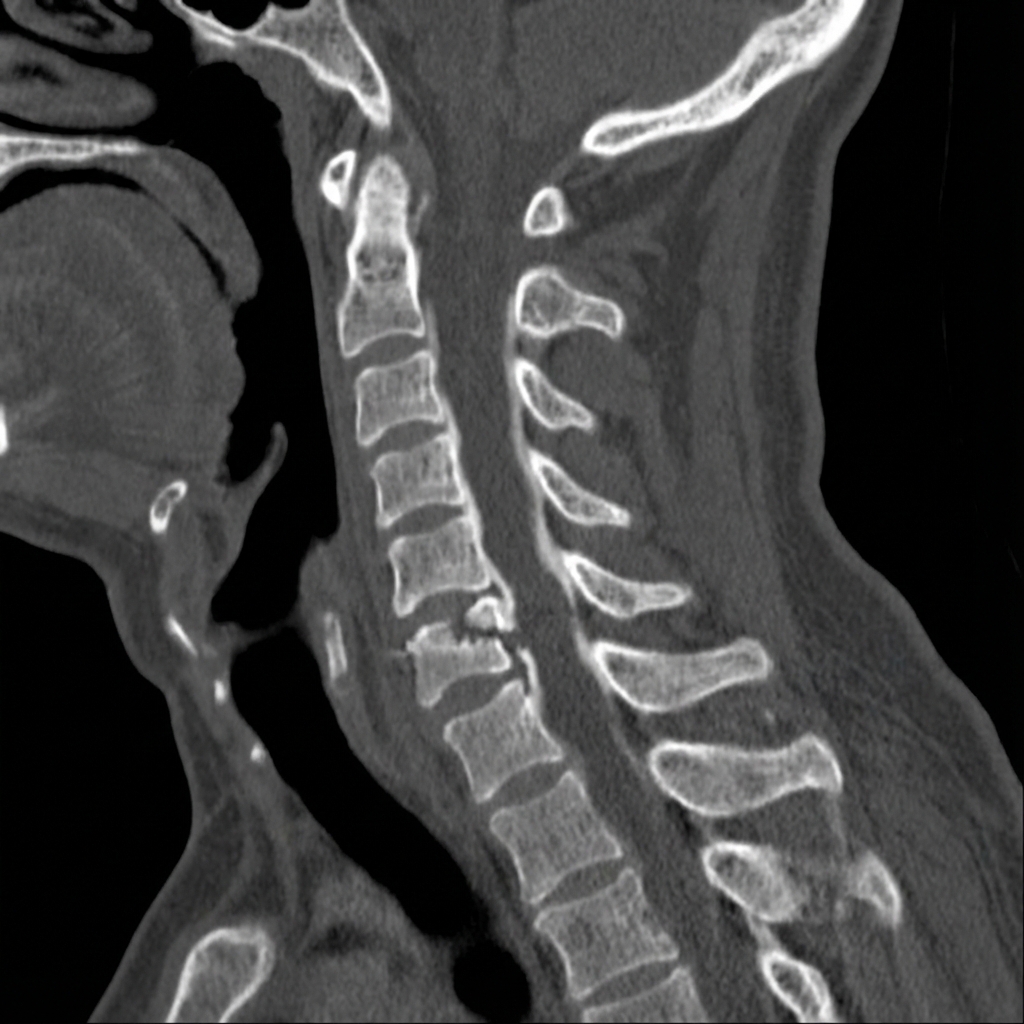

Sagittal CT demonstrating a hyperextension fracture-dislocation through a completely ankylosed cervical spine at C6-7 in a patient with ankylosing spondylitis. The fracture extends through the fused disc space and facets (three-column injury). There is posterior displacement with likely epidural hematoma. The remainder of the spine shows complete ankylosis with bridging syndesmophytes.

Describe the imaging findings and why is this injury pattern unique?